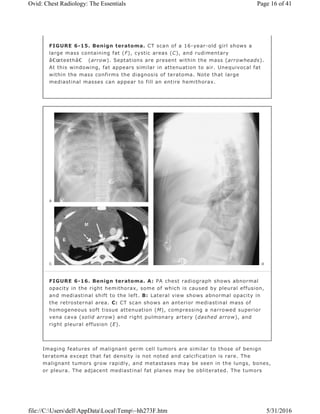

Benign teratomas are found in patients of all ages but are most common in

adolescents and young adults (Fig. 6-15). They usually produce a well-defined,

rounded, or lobulated mass in the anterior mediastinum. They grow slowly,

although rapid increase in size may occur as a result of hemorrhage, producing

imaging features suggestive of a malignant mass.

Calcification, ossification, teeth, or fat may be visible on a chest radiograph and

on CT scans. CT scans may show cystic components and/or a fat–fluid level. A

cyst wall with curvilinear calcification is often present. Unequivocal fat within the

mass confirms the diagnosis of teratoma, but the absence of fat or calcium does

not exclude a teratoma (Fig. 6-16).

FIGURE 6-15. Benign teratoma. CT scan of a 16-year-old girl shows a

large mass containing fat (F), cystic areas (C), and rudimentary

“teeth†(arrow). Septations are present within the mass (arrowheads).

At this windowing, fat appears similar in attenuation to air. Unequivocal fat

within the mass confirms the diagnosis of teratoma. Note that large

mediastinal masses can appear to fill an entire hemithorax.

FIGURE 6-16. Benign teratoma. A: PA chest radiograph shows abnormal

opacity in the right hemithorax, some of which is caused by pleural effusion,

and mediastinal shift to the left. B: Lateral view shows abnormal opacity in

the retrosternal area. C: CT scan shows an anterior mediastinal mass of

homogeneous soft tissue attenuation (M), compressing a narrowed superior

vena cava (solid arrow) and right pulmonary artery (dashed arrow), and

right pleural effusion (E).